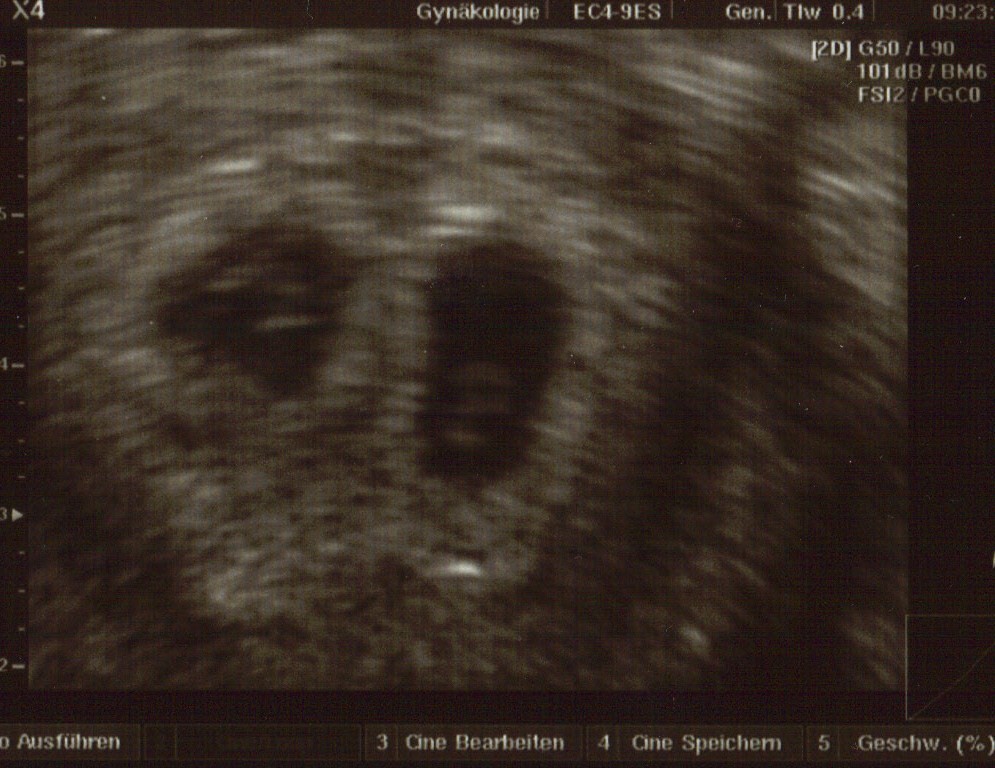

aber ich konnte es nicht sooo lange ohne ein Bild aushalten und war heute bei meinem FA hab ihm das erklärt und er meinte gar kein Thema bin heute auch 6+0 ja was soll ich sagen ich habe Zwillinge und beide Herzchen pochen, nur der eine ist einen Tag vorraus wie der ander aber er meinte das wäre bei Zwillingen normal, mein nächster termin ist in 10 Tagen habe 4 Bildchen mit bekommen ich bin echt platt vor Freude natürlich und meine Angst wächst bei 2en natürlich noch mehr das nichts passiert ;(

Mach dir echt keine Gedanken bis Dienstag ist nicht mehr lange und das Wochenende liegt ja auch dazwischen da wird sich dann was tun bei meinem 1. US in der Klinik war ich 4+3 und heute bin ich 6+0 bei mir wurde es ab dem Tf berechnet und laut dem Us stimmt es auch überein eines ist sogar einen Tag vorraus ich versuche es mal dran zu hängen aber man erkennt nicht richtig gut wa sist unscharf wenn es nicht klappt gib mir deine E mail Adresse okay???